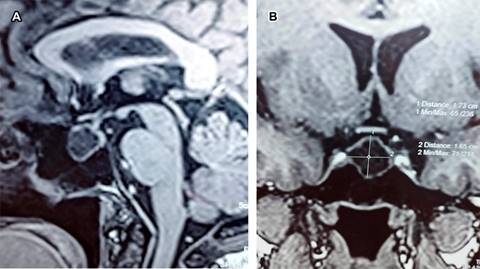

Paciente masculino de 66 años, quien cinco años atrás, por estudio de senos paranasales, se realizó tomografía axial computarizada (TAC) de cráneo en la que se encontró lesión quística en área de hipófisis. La exploración neurológica fue normal incluyendo campimetría, de igual modo los resultados de laboratorio endocrinológico fueron normales. Se realizó resonancia magnética (RM) de región hipofisiaria encontrando quiste de la bolsa de Rathke (QBR) vs quiste epidermoide (Figura 1).

Figura 1: Imágenes de resonancia magnética cerebral con medio de contraste; en (A) ponderada en T1 en corte sagital y en (B) corte coronal, se muestra proceso ocupativo intrasillar, con intensidad de líquido cefalorraquídeo de comportamiento hiperintenso, encapsulado con diámetros de 173 × 165 mm, que corresponde a quiste de la bolsa de Rathke.